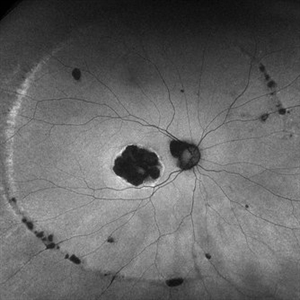

Histoplasmosis Capsulatum Retinitis OD

Histoplasmosis Capsulatum Retinitis OD

Dec 20 2021 by Brad Lovelace

Autofluorescence image of a 63-year-old woman with presumed ocular histoplasmosis syndrome OD observed for change.

Photographer: Cathy Harsma, COA

Condition/keywords: histoplasmosis, presumed ocular histoplasmosis syndrome (POHS)